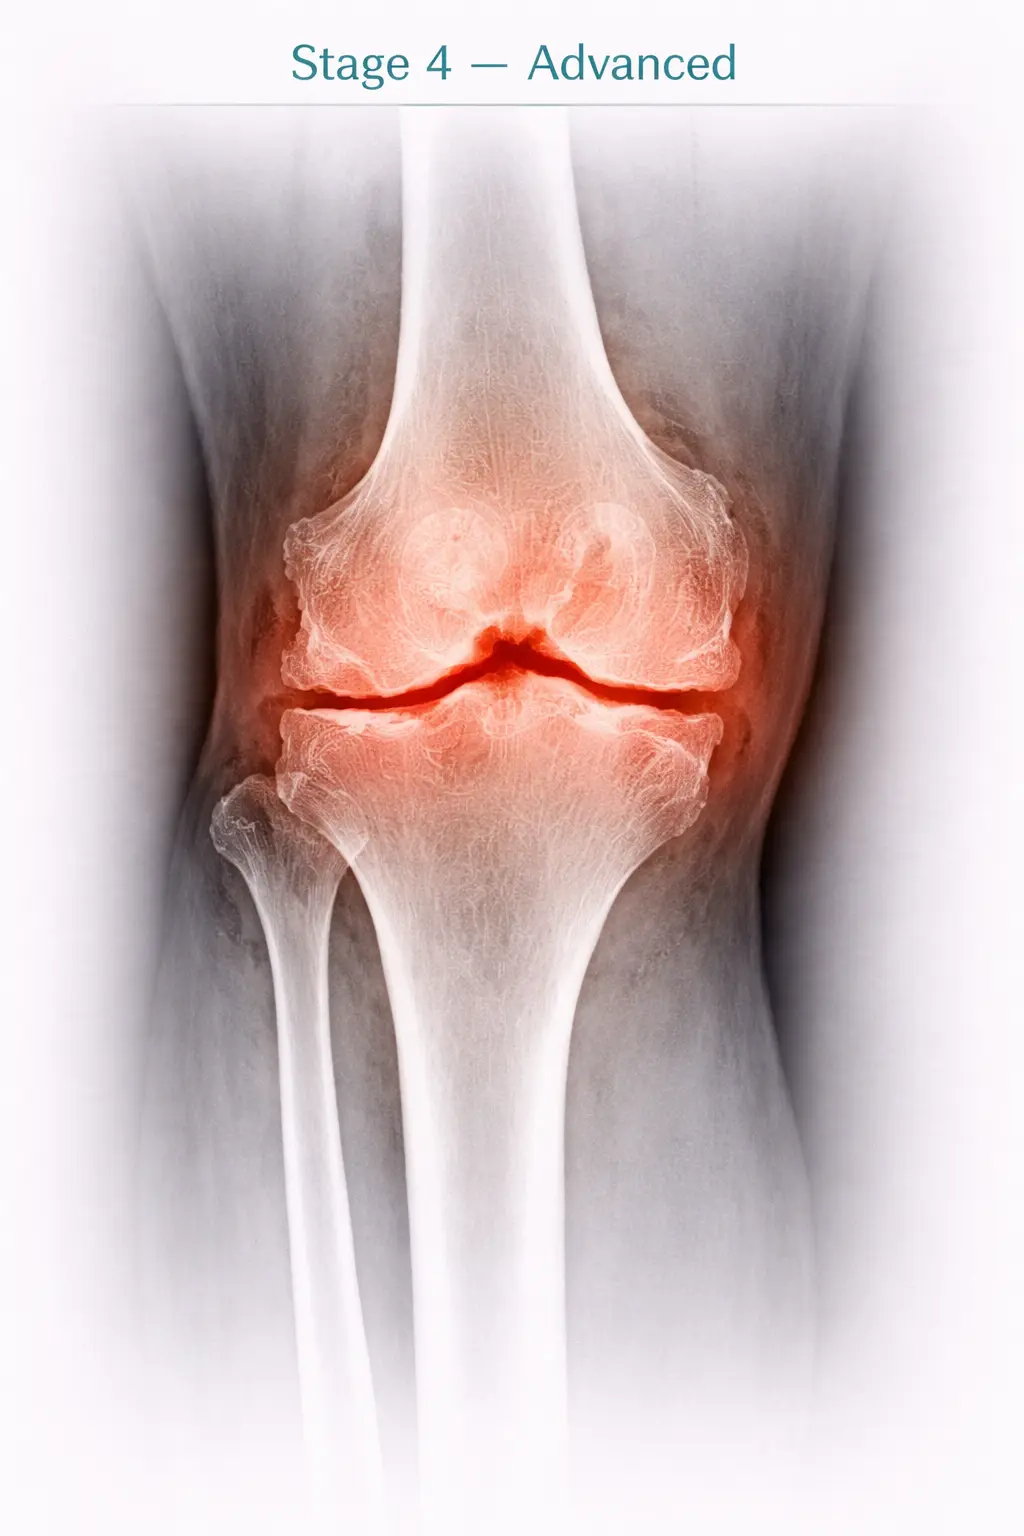

4

Stage 4

Advanced

Symptoms

• Waddling gait due to inability to take load on limb

• Difficulty in activities of daily living (ADL)

• Can't sit on the ground with crossed leg

• Avoid going out for socialization just due to pain

• Bent legs

“While going to meet relatives, a thought comes to your mind that whether he stays on ground floor or higher & would need to climb stairs which may force to avoid going there.”

X-ray Findings

• ‘Zero Space’ — Bone on bone appearance

• Rough articular surfaces — Totally lost joint — Subluxation of joint

Stage 4 - Advanced osteoarthritis in knee joint X-ray